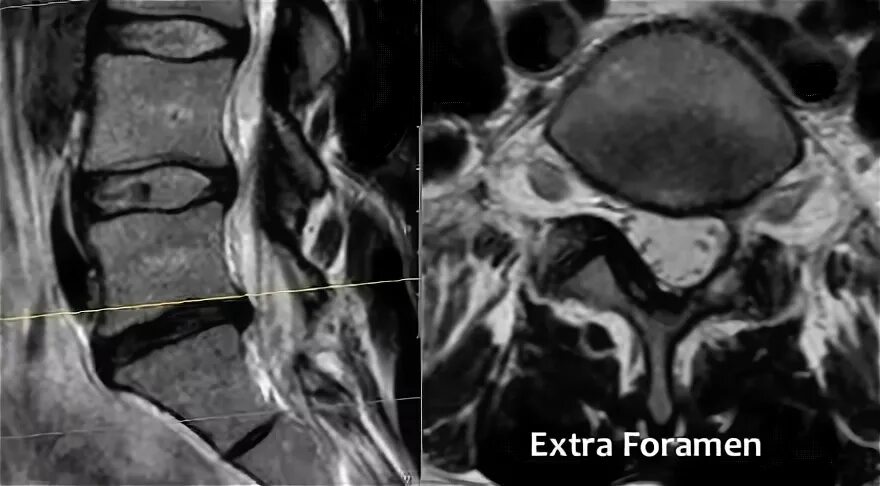

Компрессия дурального мешка что это